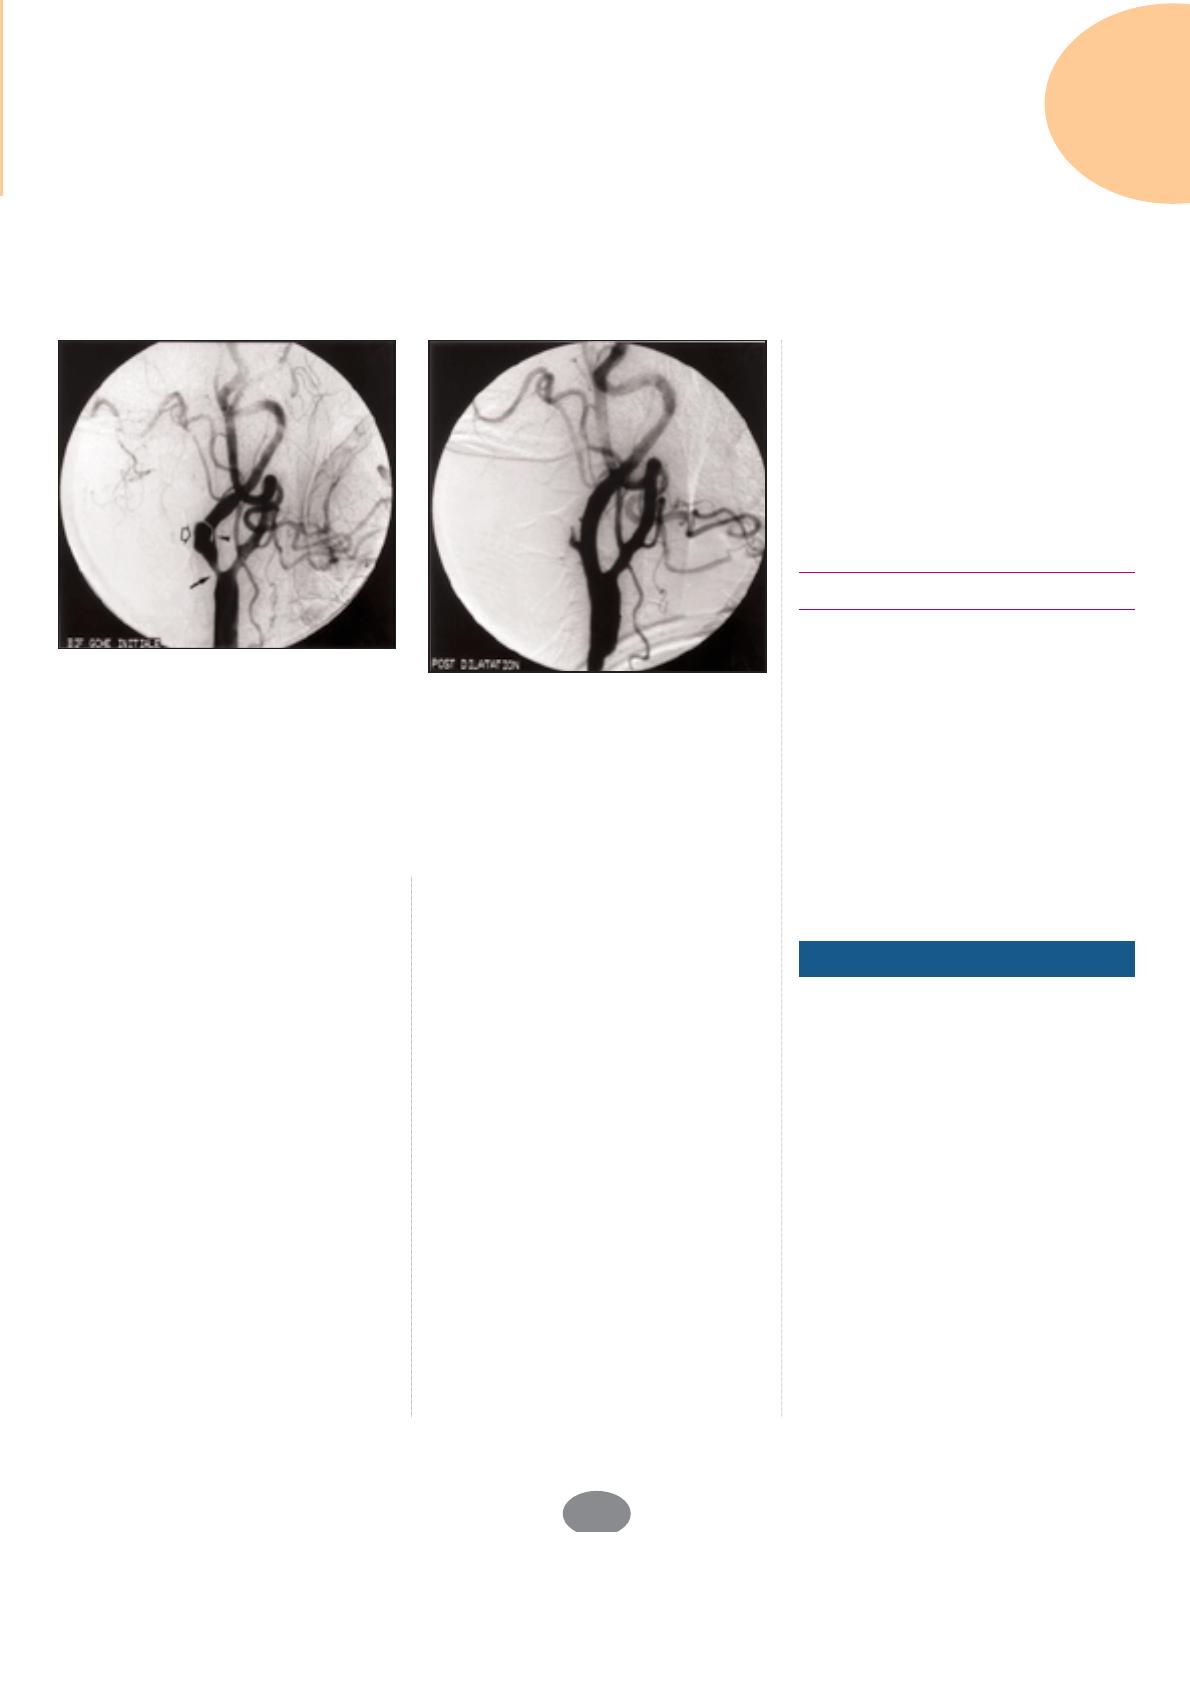

Figure 1. Angioplastie d’une sténose du siphon carotidien. Patient de 60 ans aux nom-

breux facteurs de risque vasculaire ayant présenté plusieurs épisodes d’hémiparésie

gauche.

A : L’IRM cérébrale retrouve une séquelle d’infarctus hémisphérique droit dans le terri-

toire jonctionnel entre les artères cérébrales moyenne et antérieure.

B : L’artériographie carotidienne droite retrouve une sténose serrée du siphon carotidien

(flèche).

C : Le contrôle angiographique immédiatement après angioplastie montre un aspect de

dissection (flèche fine).

D : Le contrôle angiographique après implantation d’un stent, montre la correction de

la dissection et la restitution d’un calibre artériel normal.